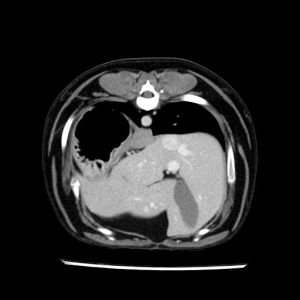

La lesione focale epatica , la ceus,la Tac e il chirurgo .